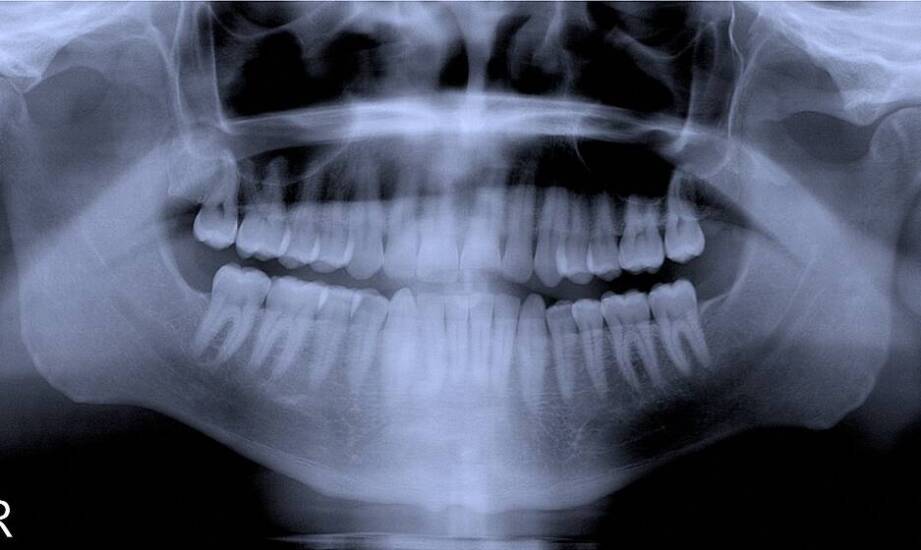

Obrazowa diagnostyka jest istotna w implantologii, gdyż umożliwia dokładną ocenę stanu kości i zębów pacjenta. Dzięki technikom takim jak tomografia komputerowa czy zdjęcia panoramiczne, lekarze mogą precyzyjnie zaplanować zabieg wszczepienia implantów. To z kolei sprzyja zwiększeniu bezpieczeństwa procedury. Warto podkreślić, że Artdent Przychodnia Stomatologiczna prowadzi różnorodne metody leczenia oraz diagnostyki w Bochni i okolicach. Zastosowanie obrazowej diagnostyki pozwala ograniczać ryzyko komplikacji oraz dostosować plan leczenia do indywidualnych potrzeb pacjentów, co wpływa na bardziej uporządkowany i komfortowy przebieg procesu wszczepienia implantów.

Nowoczesne technologie obrazowania odgrywają istotną rolę w procesie planowania zabiegu wszczepienia implantów w Bochni. Dzięki nim specjaliści są w stanie dokładnie ocenić strukturę anatomiczną jamy ustnej pacjenta, co pozwala na identyfikację potencjalnych problemów. Techniki takie jak tomografia komputerowa czy zdjęcia rentgenowskie umożliwiają zobrazowanie kości oraz tkanek miękkich, co jest niezbędne do prawidłowego zaplanowania leczenia.

W przypadku niedoboru kości lekarz może rozważyć wykonanie zabiegu augmentacji, natomiast przy nieprawidłowym ułożeniu zębów konieczna może być ortodoncja. Dzięki temu wszczepienie implantów może przebiegać zgodnie z założeniami planu, a pacjent ma szansę ograniczyć ryzyko komplikacji oraz dodatkowych interwencji. Warto zaznaczyć, że nowoczesne metody diagnostyki obrazowej są mniej obciążające i często bardziej komfortowe dla pacjentów niż tradycyjne techniki rentgenowskie, co wpływa na odbiór przygotowań do zabiegu.